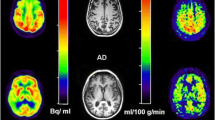

For the evaluation of cerebral blood flow (CBF) in patients with Alzheimer’s disease (AD), brain perfusion single photon emission computed tomography (SPECT) has been widely used for both visual and voxel-based analysis [1,2,3,4,5,6]. More recently, arterial spin labeling magnetic resonance imaging (ASL-MRI) has also been applied to evaluate CBF. This approach is a noninvasive technique that uses magnetically labeled water in arterial blood as an endogenous contrast medium [6,7,8,9]. Using this method to make comparisons between CBF in patients with various forms of dementia to demographically matched healthy controls has yielded significant findings. Both AD and mild cognitive impairment (MCI) have been associated with decreased CBF in the middle occipital areas, medial temporal lobe, and even more significantly in the parietal lobe [10]. Similar decreases in CBF have been reported in the posterior cingulate and precuneus, in addition to the frontal and parietal regions [11, 12]. ASL-MRI has also been successfully applied for the differential diagnosis of dementia [13, 14], and showed a high degree of concordance with FDG PET diagnoses [15, 16]. However, at present, few studies have reported voxel-wise correlations between CBF measured by ASL-MRI and cognition in patients with AD. The detection of regions with significant correlations between CBF and cognition may lend validity to the idea that regional CBF can serve as a biomarker of the neural changes underlying cognitive decline.

Using ASL-MRI, PLD1.5 scans revealed significant positive correlations with MMSE results in the right posterior cingulate cortex (PCC) and both temporo-parietal association cortexes, in addition to the right rectal gyrus (Fig 1a). PLD2.5 showed significant positive correlations in the superior parietal lobule but not PCC, and the right temporo-parietal association cortex only. Positive correlations for the right inferior temporal lobule and right fusiform gyrus were also significant (Fig 2a). Brain perfusion SPECT identified significant positive correlations in the PCC and both temporo-parietal association cortexes (right-side dominant), and the left fusiform gyrus (Fig 3a). The plots of the correlation between the voxel values and MMSE scores at the most significant area are shown in Figs. 1b, 2b, and 3b. All of them showed linear relationships. The expected voxels per cluster for PLD1.5, PLD2.5, and SPECT were 63.4, 40.8, and 60.9, respectively. Cluster-level statistics for all rendered clusters are summarized in Table 2.

From the results of our study, we identified significant positive correlations between CBF and cognition, when measuring using both ASL-MRI and SPECT. The main areas with significant results were located in PCC and temporo-parietal association cortexes, which are known to show decreases in perfusion or metabolism during cognitive decline in association with AD [25,26,27,28]. These areas are the posterior parts of the default mode network (DMN), which has a primary network center in the PCC. These regions have a strong functional connection to the left and right inferior parietal lobule (IPL), ventral and dorsal medial prefrontal cortex, and lateral temporal lobes [29]. Functional MRI studies have also consistently implicated the DMN as the most vulnerable network in AD [30, 31]. The posterior (temporo-parietal-predominant) DMN may be particularly susceptible in early-stage AD [32–34]. These studies therefore support our findings that a significant correlation exists between CBF and cognition, in the PCC and IPL. To the best of our knowledge, ours is the first report that succeeded in demonstrating such correlations between CBF and cognition using ASL-MRI, with supporting data using SPECT. These correlations may support the idea that regional CBF can serve as a biomarker of the neural changes underlying cognitive decline. As shown in Figs. 1b and 2b, the voxel values of SPM results dropped linearly with decreasing MMSE scores. Our results also showed similar significant correlations between cognition and CBF using ASL-MRI with PLD1.5 and PLD2.5, and SPECT. The measurement of CBF is thought to be influenced by modalities, tracers, and parameters. In fact, our results showed that ASL-MRI with PLD1.5 and PLD2.5 have significant differences. A significantly higher CBF was found at the adjacent areas of anterior cerebral arteries, middle cerebral arteries and posterior cerebral arteries for PLD1.5 compared to PLD2.5, suggesting early perfused areas. Liu et al. [35] evaluated the CBF of AD patients using ASL-MRI with PLD1.5 and PLD2.5, and identified lower CBF for both PLD durations at the specific area of AD pathology when compared to healthy control subjects, but with smaller clusters of voxel for PLD2.5. Despite of these significant differences in measured CBF using ASL-MRI with PLD1.5 and PLD2.5, PCC and temporo-parietal association cortexes were detected with significant correlations with cognition. This may suggest a possibility of the usefulness for the individual diagnosis using voxel-wise analyses of ASL-MRI. In Japan, voxel-wise analyses of SPECT using 3-Dimensional stereotactic surface projections (3D–SSP) [36] and an SPM-based method termed “easy Z-score imaging system (eZIS)” [37, 38] have been commonly used for the individual diagnoses in daily practices. Such voxel-wise methods may be helpful for making individual diagnoses using ASL-MRI. However, an age-specific normal database is required for the detection of significant abnormalities of individual images.